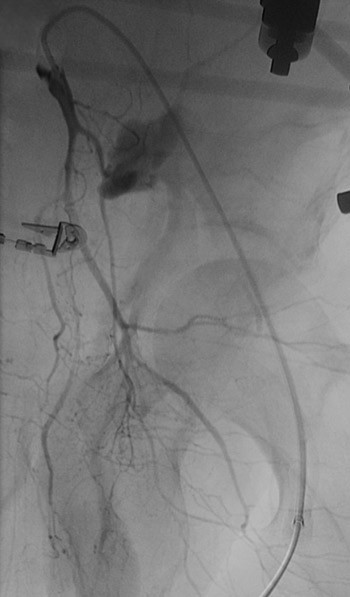

Etter konferering med radiolog ble det bestemt at man skulle utføre angiografi med embolisering. Angiografi (fig 3) viste blødning fra en tynn gren fra høyre a. iliaca interna samt fra en lumbalarterie på høyre side. Det ble utført embolisering med flere metallspiraler i sidegrener samt i hovedstammen til høyre a. iliaca interna. Deretter ble det satt flere små metallspiraler i lumbalarterien på høyre side. Til slutt ble en bakre gren fra venstre a. iliaca interna embolisert, der det var tydelig kontrastovergang til bekkenhematomet. Kontrollserier med kontrastinjeksjon gjennom føringskateter på de aktuelle stedene viste opphevet eller sterkt redusert blodstrøm. Radiologen forventet full trombosering i løpet av kort tid.